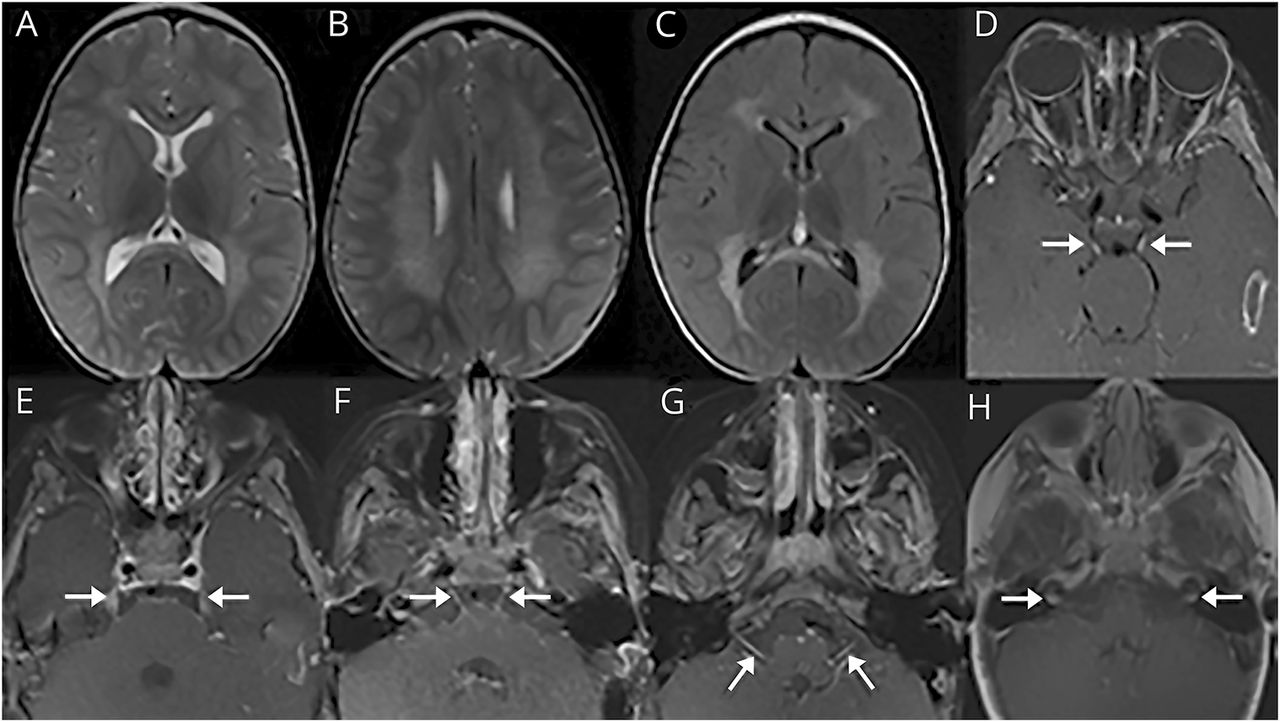

32-month-old男孩,足月出生的人,面对进步发展回归从14个月大的时候。考试,他水平眼球震颤,减少呕吐反射,过度紧张、抑郁反应。大脑MRI显示对称T2 / fluid-attenuated反转恢复支流hyperintensities在室周的白质,胼胝体,中枢semiovale(保留皮层下U纤维)增强的多发性颅神经(图)。的特点leopard-like外观hyperintensities促使进一步评价异染性脑白质营养不良(MLD)。1,2Arylsulfatase发现酶活性很低,和病人的纯合子的致病性变异ARSA基因(c.465 + 1 g),确认MLD。

轴向T2 (A, B)和fluid-attenuated反转恢复(C)图像显示对称支流hyperintensities leopard-like外观在室周的白质,中枢semiovale(爱惜皮层下U纤维)、膝、胼胝体压部。轴向超声造影T1图像显示对称增强两国第三颅神经(D,箭头),双边第五颅神经(E,箭头),双边第六颅神经(F,箭头),双边第七颅神经(G,箭头)和双边第八颅神经(H,箭头)。